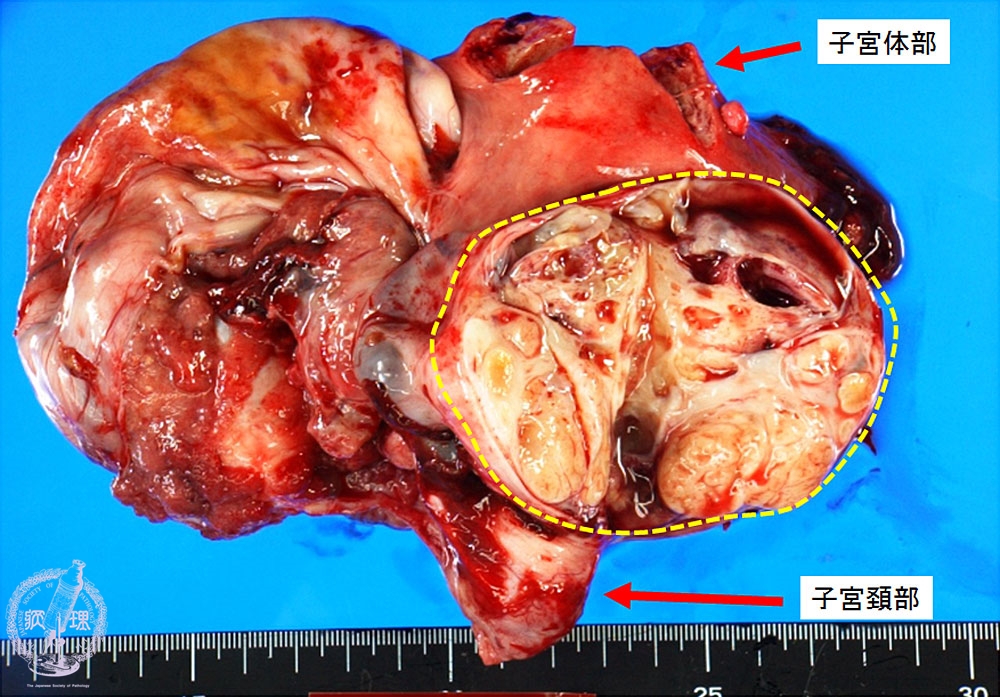

- (8)Clear cell adenocarcinoma of the ovary

Macroscopic appearance (unfixed specimen): Yellow solid tumor (yellow dotted line) in the ovarian cyst.